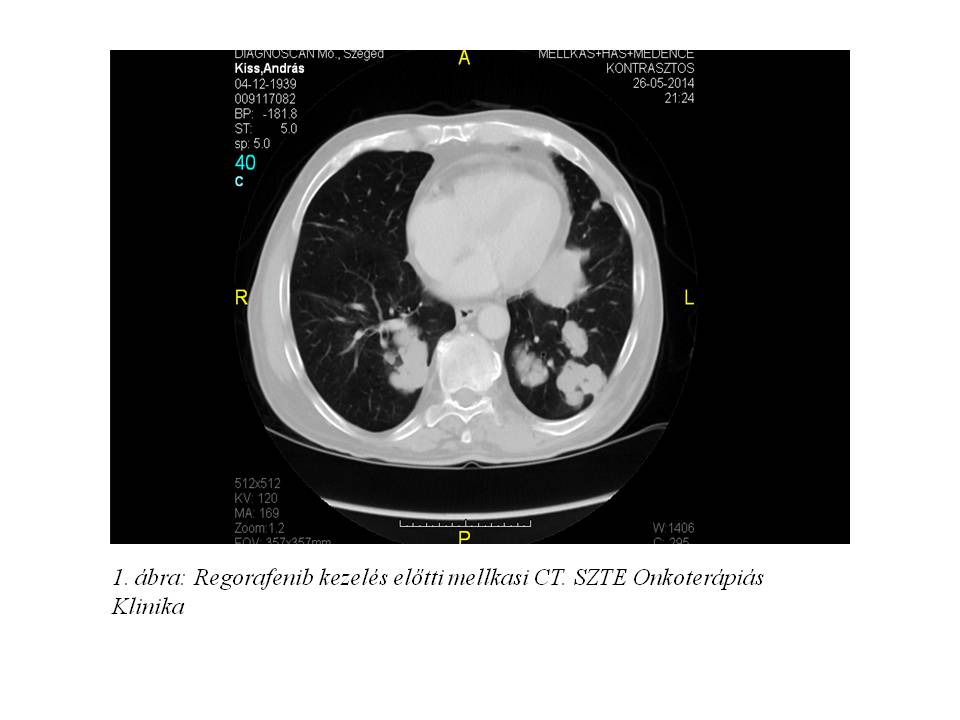

2013 augusztusban a staging vizsgálatok a hepatikus és pulmonális áttétek progresszióját írták le, mely miatt terápiaváltásra kényszerültünk. Kapecitabin monoterápia indult a korábbi 5-FU kezelés mellékhatásaként észlelt hasmenés miatt 25%-os dózisredukcióval, melyet 8 cikluson keresztül kapott a beteg. Ekkor újabb progresszió igazolódott (1. ábra, 2. ábra).

Közben, miután az EMA törzskönyvezte a regorafenibet olyan kolorektális rákban szenvedő betegek kezelésére, akiket korábban már kezeltek a rendelkezésre álló terápiákkal, Egyedi Méltányossági Kérelem került beadásra. Miután az engedélyt megkaptuk, regorafenib kezelés indult 2014 áprilisban utolsó aktív kezelési lehetőségként.